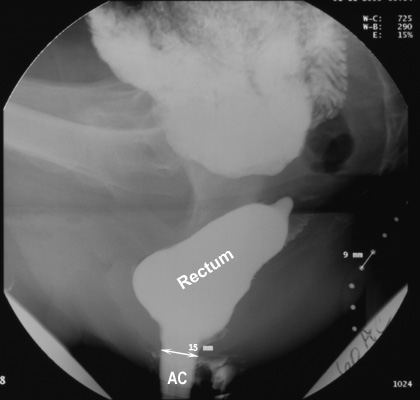

- The anal canal length is measured as the distance

between the external anal orifice and the point where the parallel

straight sides of the anal canal meet the cone-shaped walls of the distal

rectum. The mean radiographic length of the anal canal in men is 22 mm and

in women, 1.6 cm. During evacuation, the width of the anal canal averages

15 mm and seldom exceeds 2 cm.